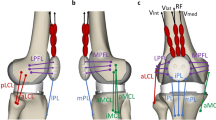

The head-neck junction geometry of the implant was designed in SolidWorks 2022 (Dassault Systèmes, Vélizy-Villacoublay, France). It comprises two components representing a neck with its trunnion and a femoral head (Fig. 1a). The so-called 12/14 taper standard was selected for its wide usage in hip implants. Although ‘12’ and ‘14’ represent the diameters in millimeters at the top and bottom of the trunnion, respectively, the taper geometry is not uniform and varies depending on the implant manufacturer4,29. In detail, according to the standard, an angle (α) of 5.7° was chosen for both the trunnion and head taper without mismatch, namely, assuming a perfect fit coupling. This assumption was adopted to maintain a consistent contact across the entire head-neck interface, thereby excluding the contribution of a variable contact area on the simulation results. Furthermore, based on common sizes provided by implant manufacturers and reported in similar studies, a diameter of 32.0 mm, with a clearance of 0.1 mm relative to the acetabular cup, was selected for the femoral head, while the neck stem was chosen to have a constant diameter of 12.0 mm35,42,43. Starting from these dimensions, a reference configuration of the junction was defined by setting a M-size head (with a taper depth of 18.7 mm) and a neck length of 38.0 mm. No moment arm was implemented for this reference configuration, meaning that the head center and the contact center are coincident. Detailed drawings of the head-neck junction are reported in the supplementary material (Supplementary Fig. S1).

Head-neck junction geometry: (a) main considered geometric features of the coupled implant components; (b) junction configurations showing the same implant offset obtained by a concurrent opposite change of both head size and neck length; (c) junction configurations showing different implant offsets by a change of the head size through the moment arm or neck length (± δ = 4.0 mm). Capital letters refer to the head size (S small, M medium, L large), black arrow indicates the parameter variation. Note: the moment arm is null when the head center and contact center are coincident.

Then, the reference configuration was modified by varying the taper depth (i.e., head size) and/or the neck length of δ = ±4.0 mm, leading to six additional configurations of the head-neck junction. The considered variations of the parameters allowed to stay within the ranges of sizes indicated by manufacturers, while maintaining the trunnion completely inside the head taper despite the investigated implant configurations, thus avoiding variation in the head-neck contact area. Specifically, two additional L-size and S-size heads were considered, having a taper depth of 14.7 and 22.7 mm, respectively. On the other hand, values of 34.0 and 42.0 mm were considered for the neck length variation. With respect to the reference, the additional configurations can present an unvaried (30.5 mm), increased (33.7 mm), or decreased implant offset (27.3 mm). Indeed, the change of only one parameter causes an offset variation (Fig. 1c). For instance, an increase in the neck length as well as a greater head size leads to a corresponding increase in the implant offset. Conversely, a concurrent opposite change of both parameters results in the same offset (Fig. 1b). For instance, an increase in neck length along with a smaller head size does not produce a variation of the implant offset. However, it is noteworthy that not all the alternative configurations resulting in the same implant offset involve the presence of a moment arm. For example, a smaller head size or, alternatively, a decrease in the neck length can produce the same decrease in the implant offset, although only the first option entails the generation of a moment arm.